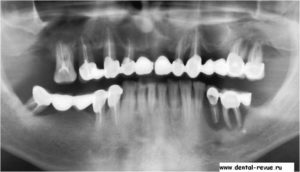

Вид больных и протезированых зубов, вы хотите себе такие зубы уже в молодом возрасте.

Кариес (некроз под действием м/о твердых тканей зуба) начинается со стадии «пятна» →поверхностный кариес → средний кариес → глубокий кариес → пульпит (воспаление («нерва») пульпы зуба) → периодонтит (воспаление периодонта)